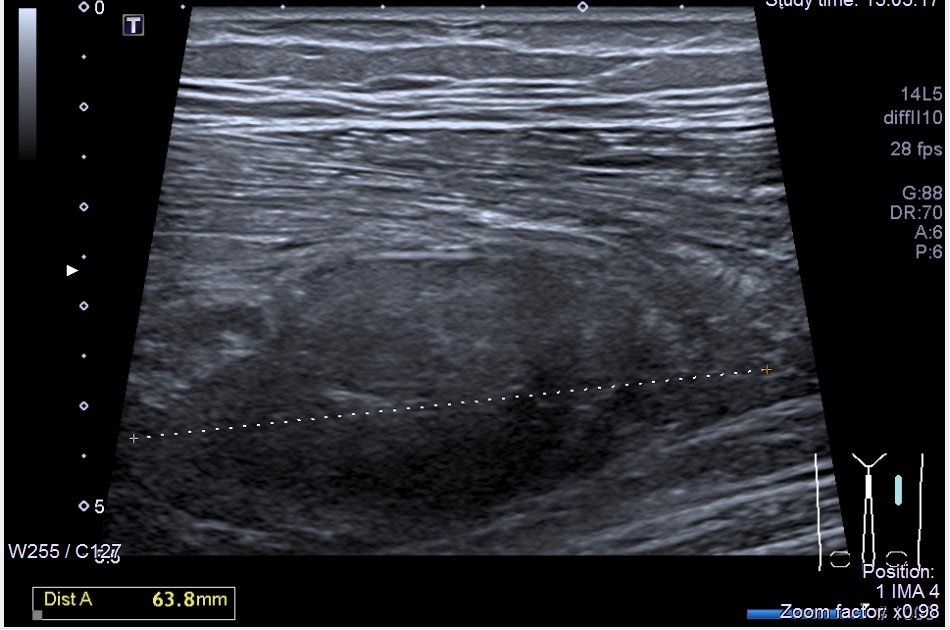

Une échographie musculo-squelettique est souvent nécessaire à l'établissement d'un diagnostic précis en cas de pathologies musculaires ou tendineuses. Le Dr Le Masle-Lastiolas est médecin échographiste spécialisé dans le diagnostic et la prise en charge de ces pathologies. Le centre Arthrosport-Argonay est équipé d'un échographe précis Canon Aplio Platinium ® permettant la visualisation de pathologies initiales ainsi que le suivi de leur évolution dans le temps.